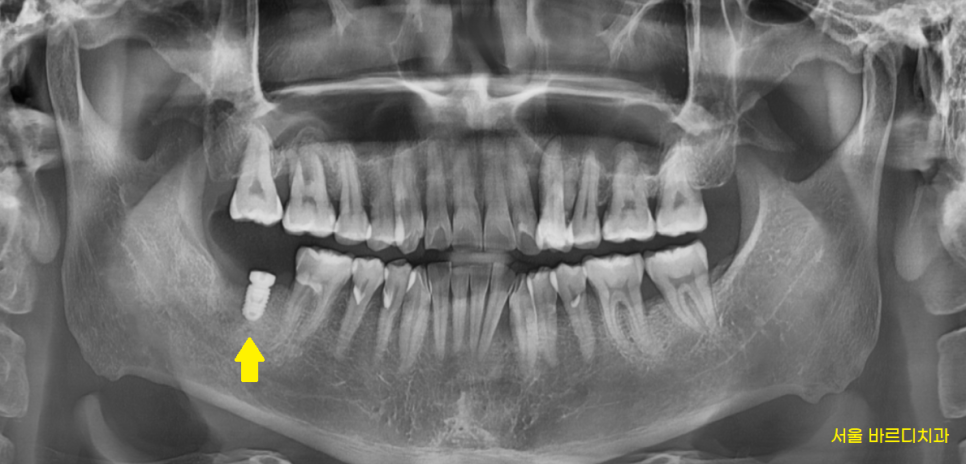

230206

잇몸 뒤쪽으로 뼈가 많이 녹았습니다.

다행히 앞쪽 뼈는 치아 뿌리를 붙잡고 있는 상황입니다.

잇몸치료를 계속 받고 있는 상황이었지만

잇몸 뒤쪽 뼈가 더 녹아있습니다.

발치 후 임플란트 해야함을 설명드렸는데요